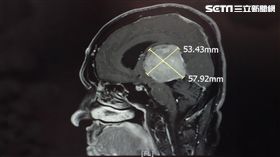

正妹「體重暴增」減不下來 醫檢查驚呆

要是生活習慣沒有太大改變,但體重卻突然大幅增加,可能...